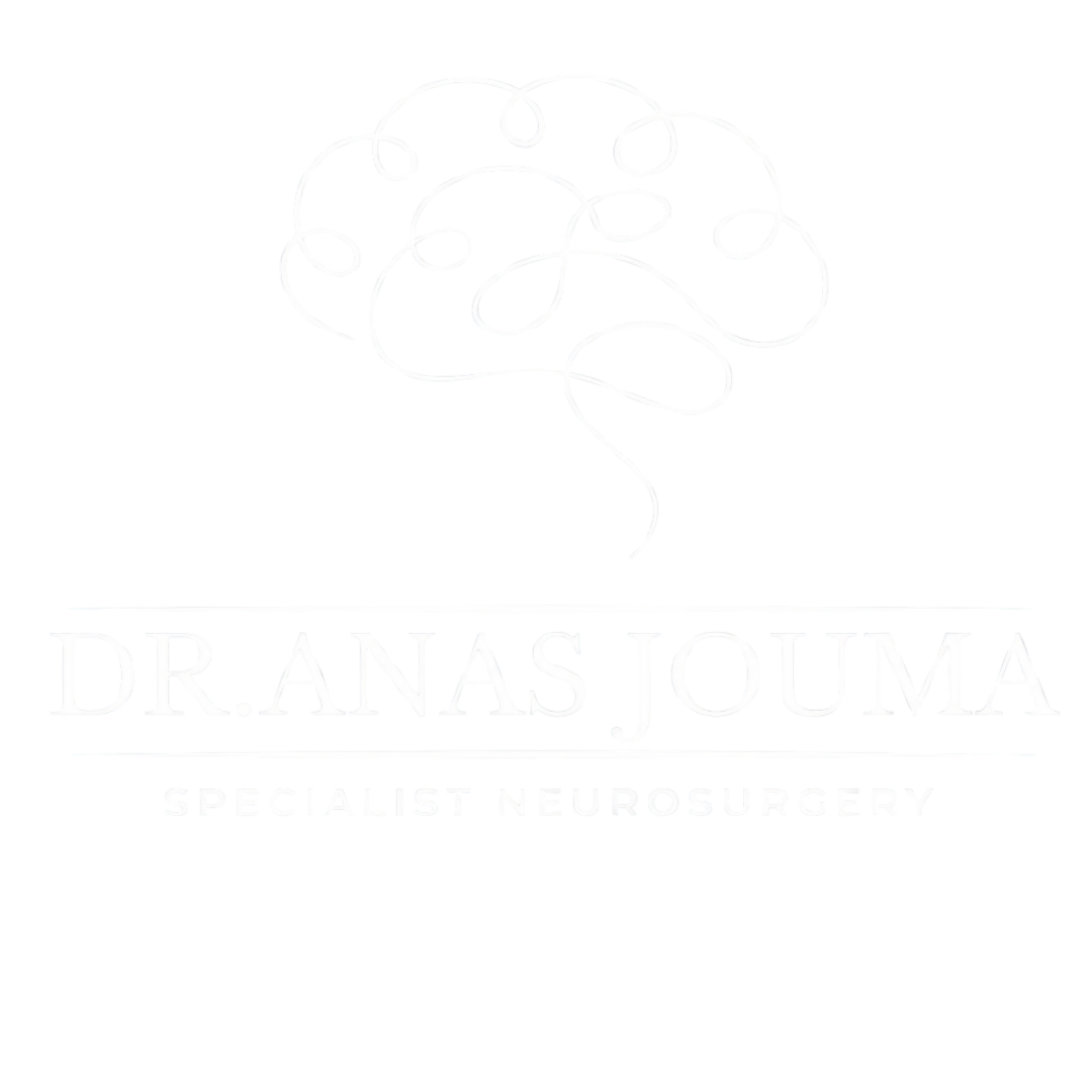

Surgical Correction

Surgical Correction

Scoliosis Realignment

Correcting structural spinal deviations using high-precision stabilization to restore the natural axis of the vertebral column.